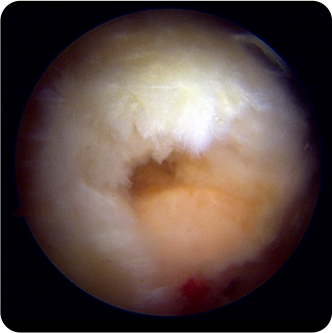

회전근개파열의 여러 모습들

회전근개파열의